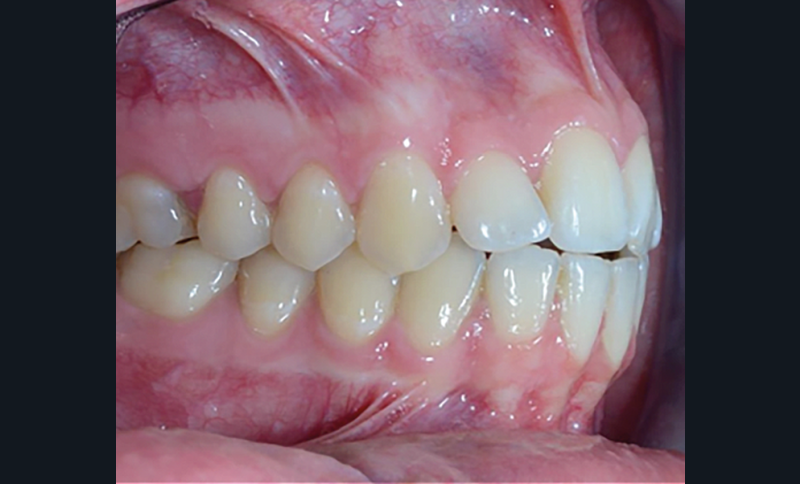

C’est à ces questions que nous permettront de répondre les deux premiers conférenciers, parodontologistes : le Dr Béatrice Straub nous présentera le renfort parodontal minéralisé, technique qu’elle a développée et pratique depuis de nombreuses années, pour éviter les préjudices des mouvements orthodontiques à risque, notamment lors des décompensations préchirurgicales (fig. 1a-d) ; le Pr Anton Sculean abordera le thème des greffes, avec leurs indications, les différentes techniques à privilégier et illustrera ses propos par de nombreux cas cliniques aux résultats esthétiques impressionnants.